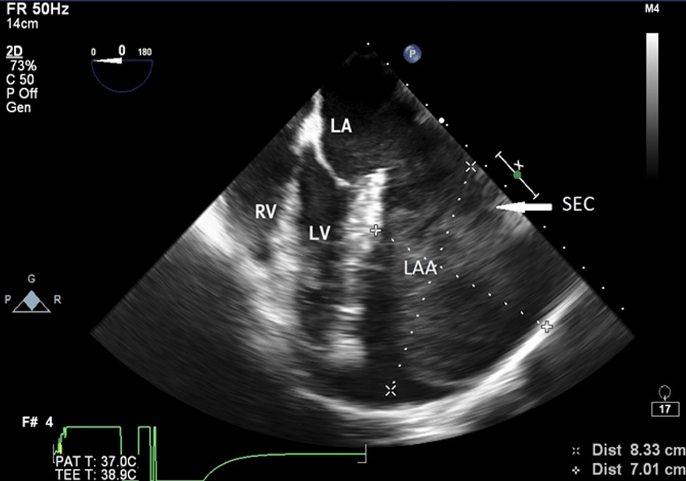

A 22-year-old woman was admitted at our institution in May 2018 with intermittent episodes of chronic atrial fibrillation, angina and dyspnea on exertion New York Heart Association Class-IV. She had three episodes of transient loss of consciousness with no neurological deficits. Notable clinical findings included an intermittently irregular pulse, blood pressure of 90/60 mmHg, cardiomegaly with normal heart sounds and no murmur. The electrocardiogram demonstrated atrial fibrillation, left atrial enlargement, normal axis and voltage. The chest roentgenogram revealed an enlarged cardiac silhouette with a prominent convex bulge of the left upper cardiac border without hilum overlay sign and carinal widening (Figure 1). Transthoracic and transesophageal echocardiogram revealed a giant left atrial aneurysm (8.33 x 7.01 x 4.0 cm) with a wide neck (4.0 cm). The aneurysm extended to the apex of the left ventricle and was entirely intrapericardial and did not show any intraluminal thrombus (Figure 2). The left ventricular diameter and wall motion were within the normal limits. She had moderate dysfunction of the left ventricle (left ventricular ejection fraction=0.35). The interatrial septum and the heart valves were all normal. The visceral layer of the pericardium appeared to be intact.

Figure 2: Transesophageal Echocardiographic midesophageal four chamber view at 0 degree showing aneurysmal left atrial appendage (8.33 x 7.01) with spontaneous echocontrast

LA: left atrium, LV: left ventricle, RV: right ventricle, LAA: left atrial appendage, SEC: spontaneous echocontrast